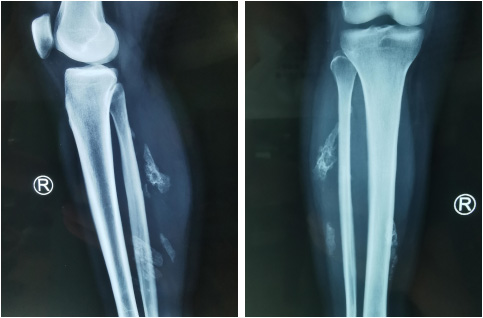

王女士找到手外三病区的陈步国主任就诊,陈主任查体时发现,患者的肿物位置比较深,质地较硬,活动度差,与周围组织分界不清楚,按压有触痛。于是陈主任给王女士开了X线片的检查单。影像学检查结果显示,在王女士的左小腿肌肉里发现了多处骨化病灶,类似肌肉里长了骨头。经过病史询问、查体和影像学检查,陈主任初步判断王女士得了“骨化性肌炎”,需要手术切除肿物,并通过病理检查进行最终诊断。

X线片